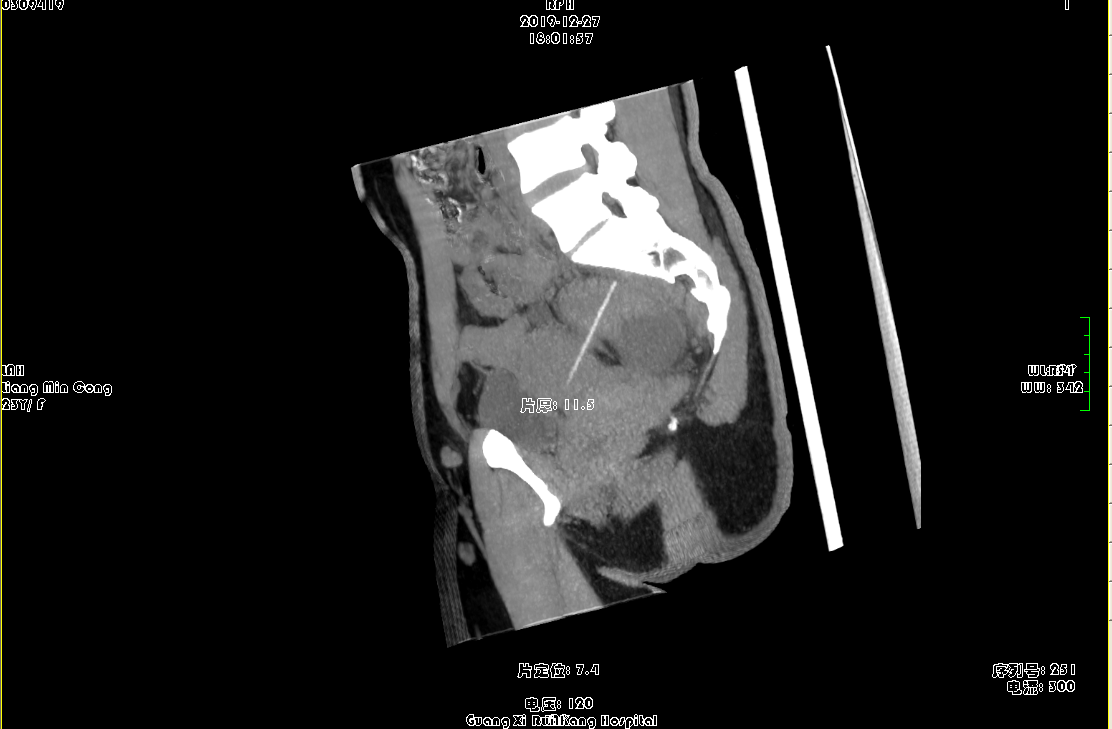

盆腔CT平扫+增强:

1.子宫左后壁至直肠后壁条状高密度影并突破子宫壁、肠壁,异物存留?请结合临床;

2.右侧附件区类圆形囊状影,卵巢囊肿?

3.右侧附件区管状囊状影,输卵管积水?盆腔包裹积液?其他?请结合其他相关检查;

4.宫体左侧旁囊状影,左侧附件囊肿?淋巴管囊肿?